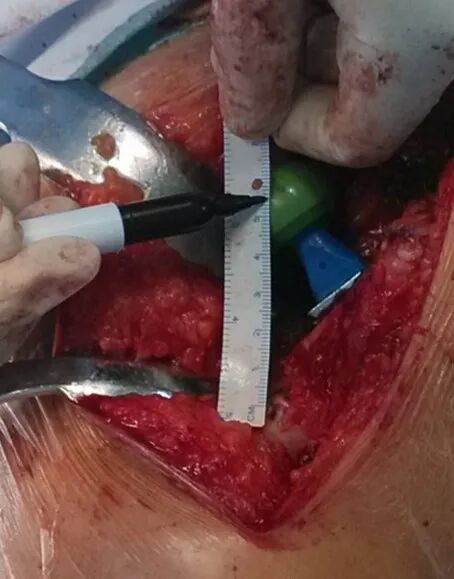

切开复位

术中评估-根据模板测量的信息-需考虑手术体位-手摸心会-术中X线摄片

术中评估1、用手指感觉臀中肌张力2、直接比较两肢体长度----不是很可靠

-将髌骨和足跟置于同一水平

3、触摸髂胫束张力4、Drop-kick test (将髋关节置中立位,屈曲膝关节至90度,如果肢体过长,放松膝关节时,膝关节有自行伸直活动)5、Shuck test(髋关节中立位牵拉下肢,头臼分离0.5 – 1cm左右)